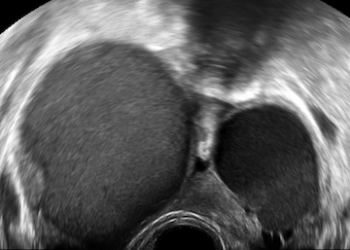

Per il mese di Dicembre SIEOG Giovani presenta il Webinar sullo screening delle cardiopatie congenite nel primo trimestre. La registrazione...